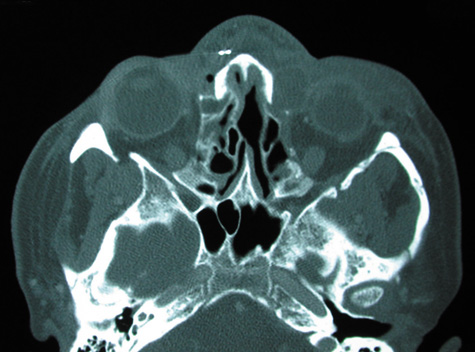

CT is particularly useful for imaging orbital and subperiosteal abscesses. Because the periorbit is not adherent to the orbital walls except at the suture lines, an abscess lifts the periorbit, creating a convexity in the orbital periosteum (Fig. 16). Usually subperiosteal abscess formation occurs adjacent to the involved sinus,25,64 but occasionally it occurs at a remote location such as the superolateral orbit.65 Gas may be found within a subperiosteal abscess or within the orbit, arising either from gas-forming bacilli or free communication with sinus air or from prior trauma (Fig. 17). 57,66 CT cannot accurately predict whether a subperiosteal mass represents exudate, inflammatory transudate, or hematoma.67,68

Fig. 16. Computed tomography showing subperiosteal abscess formation. Note elevation of orbital periosteum and convexity as pus elevates periorbit from the medial orbital wall.